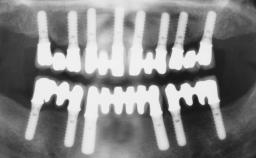

Immediate Loading of Four Implants in the Mandible and Six Implants in the Maxilla and Final Restoration with a Full-Arch Metal Framework FDP and a Full-Arch CAD/CAM Zirconia Framework FDP

A 65-year-old female patient with a failing residual maxillary dentition and a complete mandibular removable denture was referred for consultation and treatment. The patient’s chief complaint was that her upper residual teeth were mobile and she was unable to chew. The patient also asked us to improve the esthetic appearance of her smile. The patient’s desire was a stable and comfortable dentition in both jaws, and she specifically asked for a fixed rehabilitation. The patient reported a history of recurrent caries, endodontic complications, and periodontal disease as main reasons for previous teeth extractions. The anamnesis was negative for bruxism and TMJ disorders. The patient had no systemic diseases, was not on any medication,and did not smoke. The extraoral examination revealed a medium lip line, a wide diastema between the two central incisors (which, according to the patient, had appeared recently), and a partial collapse of the perioral soft tissues, probably due to loss of the correct vertical dimensions.

# of Implants 10

Defining Characteristics Fully edentulous upper jaw to be rehabilitated with four or more implants

Modality Fixed hybrid bridge on 5+ implants

Defining Characteristics Fully edentulous upper jaw to be rehabilitated with an implant-borne fixed dental prosthesis